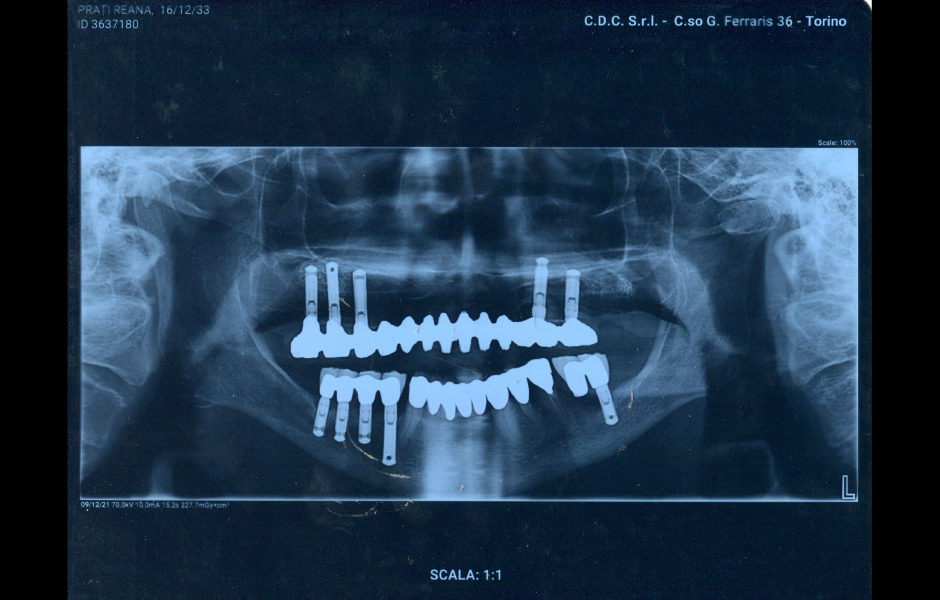

Na RTG snímku byla patrná prosvětlená oblast obklopující implantát v místě zubu 14 a nálezy v apikálních zónách zubů 35 a 44 (obr. 7). Po odstranění horní náhrady bylo zřejmé, že implantát v místě zubu 14 má značnou pohyblivost a je indikován k odstranění.